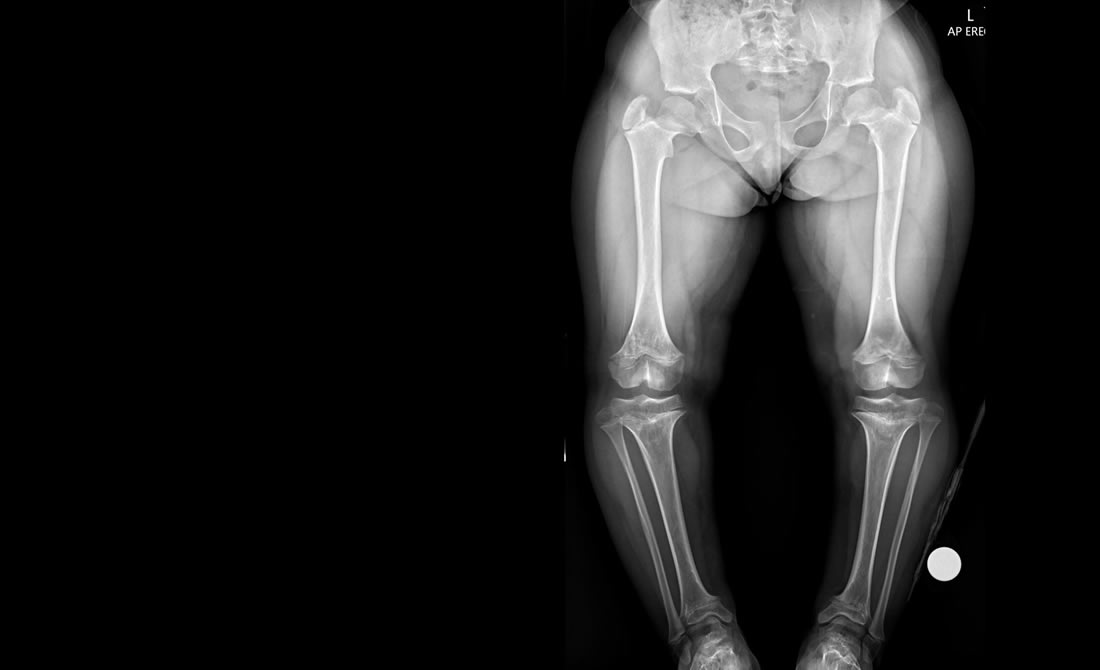

Achondroplasia / Skeletal Dysplasia

Achondroplasia and other Skeletal Dysplasia is the most common type of short-limbed dwarfism. The condition occurs in 1 in 15,000 to 40,000 newborns.